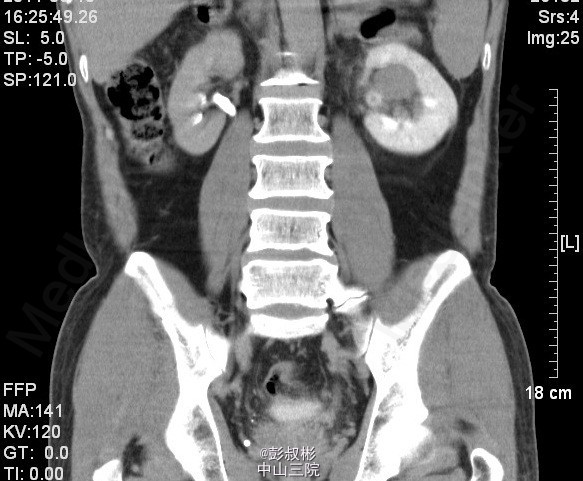

男性,51岁,发现左肾肿物2年余。反复左腰部隐痛2月余,无肉眼血尿。泌尿系B超:左肾中极见一个类圆形低回声光团,大小:30×26mm,边界不清,内部回声欠均匀。左肾实性占位病变。腹部CT:左肾占位病变,考虑为肾癌可能性大。